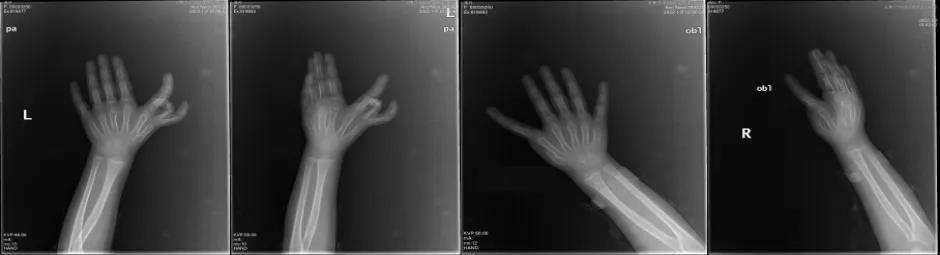

1月13日,玉林市中西医结合骨科医院手外二科梁再卿主任带领团队为一个患有罕见的手先天畸形的小女孩成功完成了拇再建手术,力求视觉美观及功能最大化,为患儿带来了新希望。小女孩姓潘,4岁,看起来比同龄人要成熟许多。因为出生的那一刻就注定了她的“与众不同”,所以在成长的道路上也注定了会遭遇不一般的经历,从简单的玩玩具、做游戏,到穿衣吃饭,再到写字学习,每走一步都比别人困难,这样的“与众不同”带来的心灵创伤可想而知。从这小女孩身上我们可以感受到“受苦受难的孩子早成熟”,又是什么苦难困扰着小女孩和她的家人呢? 原来小女孩得了一种罕见的先天性疾病,叫作镜影手畸形。小女孩左手有7个手指,右手有6个手指。其中左手5个手指外观及功能发育相对正常,还有2个手指明显细小畸形,无功能;但是没有拇指和大鱼际,拇指功能占全手功能的40%,外观和功能都不好。为此于2021-06-01到其他医院行右手桡侧多余1指切除术,而左手问题没有得到解决,小女孩和她的家人仍旧无法从这个疾病的阴影里走出来。

那么,什么是镜影手畸形?镜影手畸形也称为尺骨复肢畸形,在先天性手部畸形中归类为重复畸形,是累及整个肢体的罕见先天性疾病。在上肢先天畸形流行病统计中,镜影手畸形是最罕见的,在人群中的发病率难以获得统计。上肢畸形典型表现为尺骨重复,桡骨缺如,包含七指或八指的多指畸形,拇指缺如等。具有一定的遗传性,小女孩的爸爸和奶奶都是多指畸形,所幸的是,小女孩是非典型镜影手畸形,除了手部畸形外,其他部位都是正常的。那仅仅是切除多余的手指并不能令小女孩及家属满意。为了从外观及功能上解决问题,小女孩父母慕名来到玉林市中西医结合骨科医院手外二科,希望梁主任可以解决他们的困扰。梁主任通过病情分析,认为有三个手术方案:一是仅桡侧多余2指切除术,二是桡侧多余2指切除+顶端移位术,三是桡侧多余2指切除+拇重建术,越是要求外观美观化和功能最大化,手术就越难越复杂。经过与家属沟通,达成一致意见:要做就要往最好的方向做。 1月13日,梁再卿主任团队为小女孩进行了手术。术前巧妙设计切口以及截骨位置,术中精细解剖避免损伤神经血管,历时两个小时左右,手术顺利,受区外观漂亮,供区直接关闭且美容缝合。

图为术前手术切口的设计

图为术前截骨水平设计,红色为切除骨质